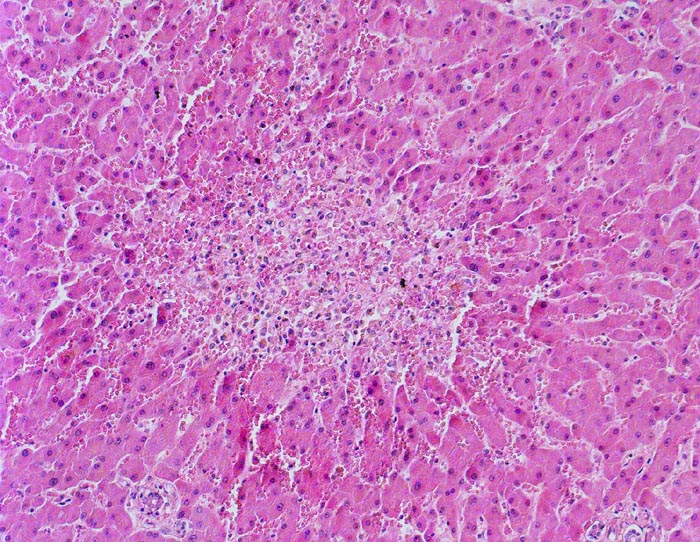

Linksherzversagen oder ein Schockzustand können zu einer hepatischen Minderperfusion mit ischämischen Koagulationsnekrosen der perivenulären Hepatozyten führen. Die Kombination von Hypoperfusion und retrograder Stauung (Rechtsherzversagen) führt zu zentrilobulären hämorrhagischen Nekrosen. Klinisch führen diese Nekrosen zu einer transienten geringen bis mässigen Erhöhung der Transaminasewerte, gelegentlich auch zu einem leichten Ikterus.

Metastasierendes Kolonkarzinom. Als Todesursache fanden sich nicht ganz frische zentrale und perizentrale Lungenembolien.